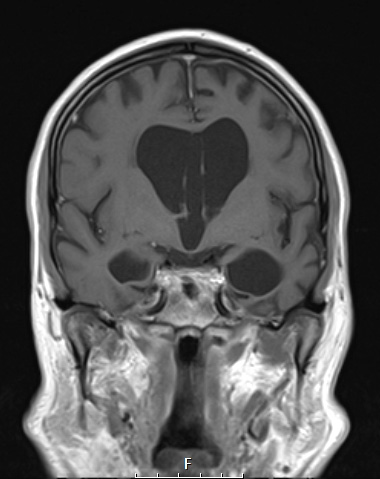

A T1-weighted coronal image demonstrates the frontal and temporal lobe atrophy with a hint of superior temporal gyrus sparing.